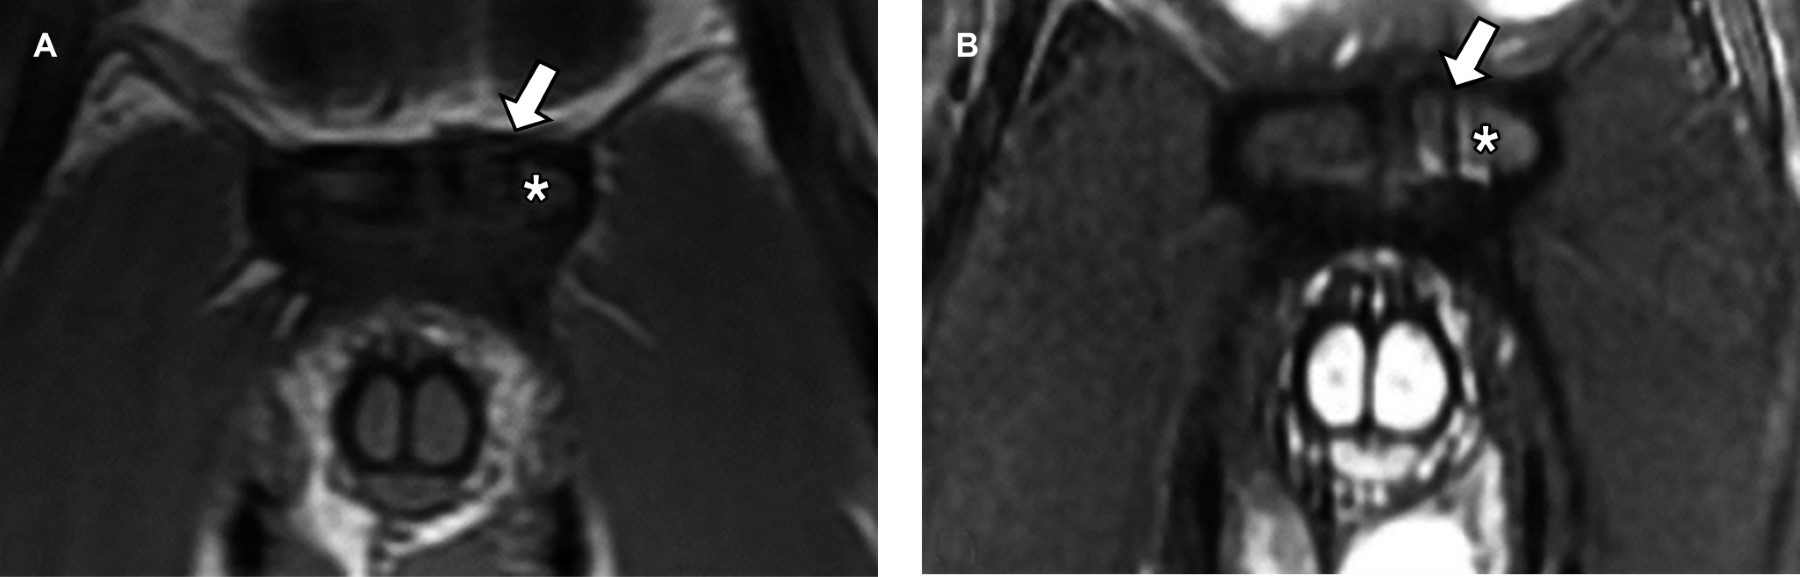

Athletic pubalgia is a clinical syndrome characterized by chronic inguinal pain secondary to muscle, tendon, or bone injury at the pubic bone level. It is a confusing diagnosis because there is a wide spectrum of pathologies that cause inguinal pain, and the clinical picture is nonspecific. In these patients, the magnetic resonance imaging (MRI) study plays a fundamental role in providing an accurate diagnosis.

Figure 2